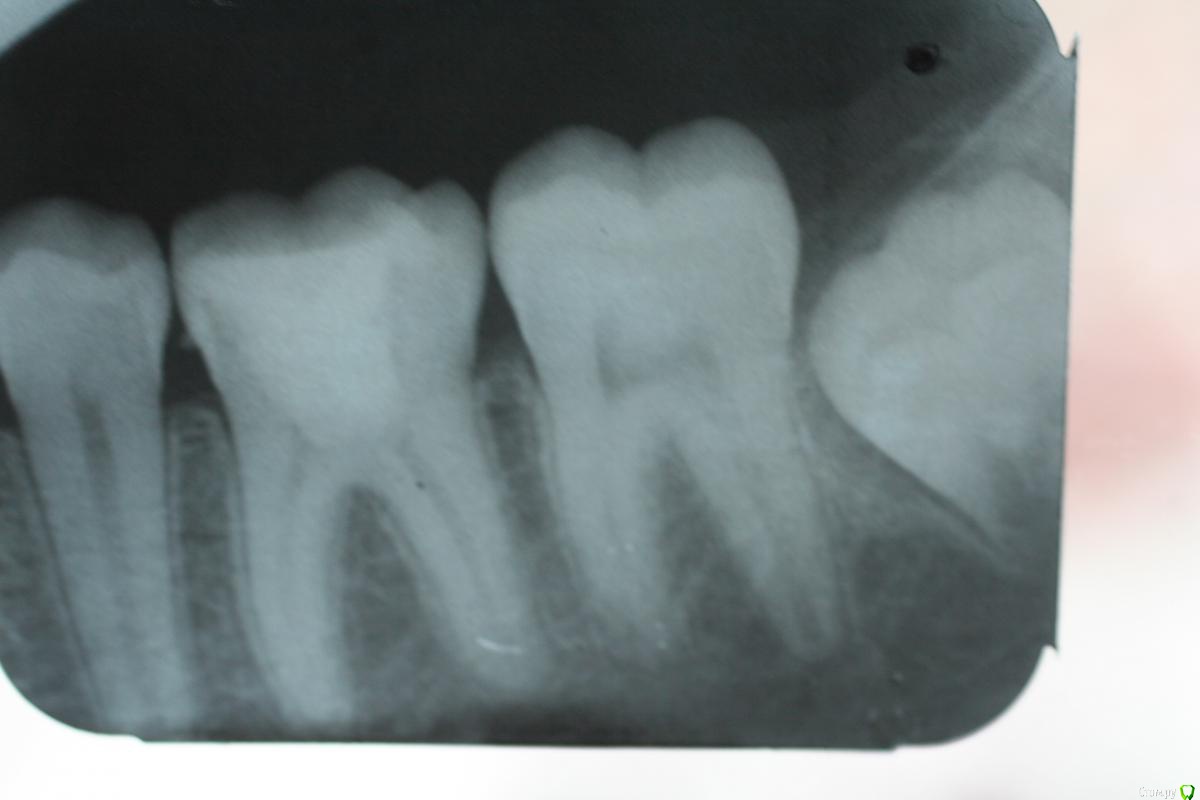

Stom22 Опубликовано 29 августа, 2014 Поделиться Опубликовано 29 августа, 2014 Сегодня пришла пациентка 14 лет, с болью в 37 от сладкого. На рентген. снимке полость кариозная находится очень близко к пульпарной, верхушки несформированы. Знаю, что в таких зубах надо временно пломбировать Ca под постоянную пломбу из фотокомпозита на срок формирования верхушек корней. Появились вот такие вопросы: каким Ca лучше пломбировать в таких случаях (метапексом, каласептом или др.)? Какой метод экстирпации использовать: витальный или девитальный? Можно ли ставить мышьяковистую или безмышьяковистую пасту в такой ситуации? Если да, то на сколько по времени? Как и чем обрабатываете каналы в таких ситуациях (какими файлами, какой номер используете для первичного прохождения таких каналов, они ведь широкие изначально, до какого размера расширяет)? Чем и как пломбируете (каналонаполнителем или Са из канюли), пломбируете на рабочую длину или минус 1 или 2 мм? Как апекслокатор реагирует на такие каналы, не врёт ли? С такими зубами никогда не сталкивалась, в основном работаю со взрослыми. Кто имеет такой опыт, если не трудно, поделитесь своими знаниями в этой области. Можно и в личку. Ссылка на комментарий

Masha01 Опубликовано 26 февраля, 2016 Поделиться Опубликовано 26 февраля, 2016 Между первым и вторым фото два года. Апексогенез на мта. Ссылка на комментарий